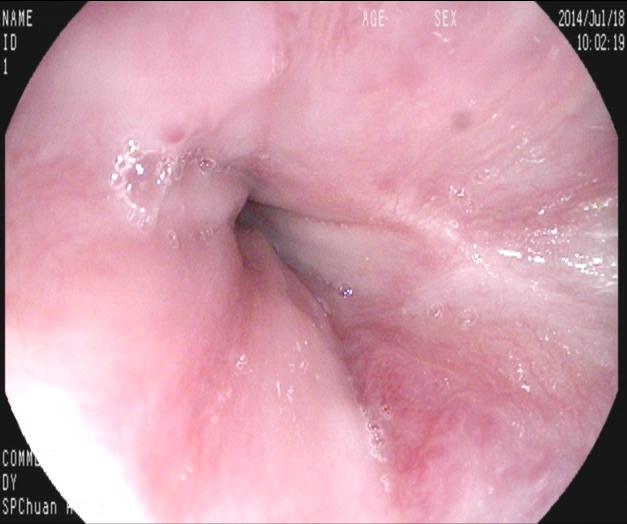

【九個(gè)月后復(fù)查】

九個(gè)月來(lái)患者無(wú)黑便及嘔血,復(fù)查胃鏡,食管內(nèi)曲張靜脈基本消失,胃底曲張靜脈亦減輕?;颊咴俅纬鲅L(fēng)險(xiǎn)而減低。如下圖:

上2圖為胃底,原團(tuán)狀曲張靜脈亦消失。